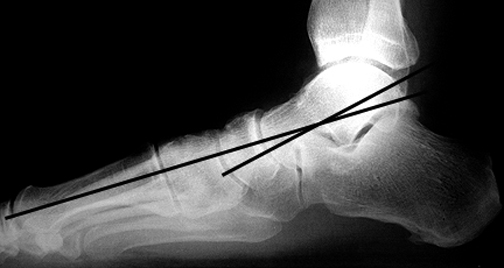

This is an angle formed between the long axis of the talus and first metatarsal on a weight bearing lateral view fig a. Because we had few patients with complete ptt rupture or advanced stage flatfoot deformities in this study it is not surprising that meary angle had the highest association with ptt tear. Hometxt last modified. A calcaneal pitch of less than 170 or 180 indicates flat feet.

Hindfoot valgus where the talocalcaneal angle is 350 talonavicular uncoverage or subluxation. Probably the most familiar line to radiologists and a more direct measurement of pes planus or collapse of the longitudinal arch is the talar 1st metatarsal angle mearys angle 3. Among all the measurements in our study meary angle had the best association with ptt tear as diagnosed on mri. 20160814 0133 external edit page tools.

An angle greater than 40 convex downward is considered a flat foot. Pes planus is a deformity of the foot where the longitudinal arch of the foot is abnormally flattened and can be congenital or acquired. Carrying angle of the elbow. Same lateral x ray showing the measurement of mearys angle which is the angle between the long axis of the talus and first metatarsal bone.